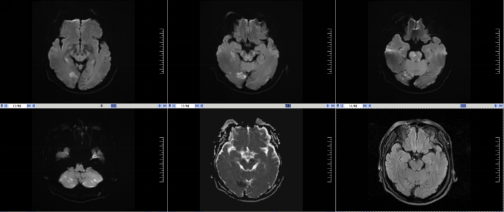

图2 取栓术后患者闭塞的基底动脉再通,血供良好

急查头颅磁共振显示:脑干小脑多发急性脑梗死,基底动脉闭塞。该患者DWI-T2FLAIR序列不匹配,符合静脉溶栓指征,积极与病人家属沟通后,行静脉溶栓。静脉溶栓后患者症状无明显改善,下一步怎么办?患者还正值壮年,如果就这样保守治疗预后较差,患者可能丧失劳动能力!跟我的上级医生黄圣明老师汇报情况后,决定进一步桥接介入治疗,遂联合介入科刘要先主任急诊为患者行“脑血管造影+经皮颅内动脉取栓术”,取栓术中可见患者闭塞的基底动脉再通,血供恢复。术后送ICU观察。